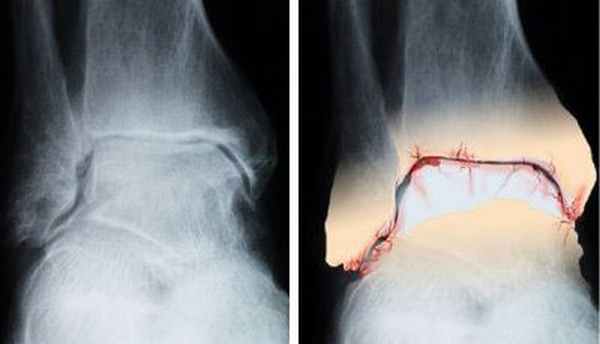

Деформирующий артроз голеностопного и подтаранного сустава – дегенеративно-дистрофическое заболевание, при котором происходит разрушение суставного хряща с последующим изменением суставных поверхностей костей. Другими словами, это преждевременное старение и постепенное разрушение тканей сустава. Хрящ сустава становится тонким и ломким. Трущиеся поверхности сустава утрачивают способность к скольжению. Связки становятся менее эластичными и менее прочными. В тканях сустава при артрозе появляются микроскопические разрывы, сустав деформируется. В результате – боли, воспаление и ограничение подвижности.

Механизм развития остеоартроза заключается в постепенном разрушении тканей образующих сустав. Травмы, в том числе и микроскопические нарушения питания хряща приводят к тому, что он начинает истончаться и теряет свою прочность. В результате возникают очаговые разрушения хряща, которые затем все больше распространяются. Количество жидкости в суставе уменьшается, суставная сумка утолщается. Возможно развитие воспаления синовиальной оболочки (синовита). Происходит разрастание костной ткани, принимающей участие в образовании сустава, что приводит к его деформации. Поэтому это заболевание и называют деформирующим остеоартрозом. Все эти изменения приводят к нарушению нормальной работы сустава.

Артроз голеностопного сустава – активный дегенеративный процесс, результатом которого является полное разрушение тканей сустава. Просвет суставной щели постепенно уменьшается, поверхность костей теряет гладкость, на них появляются прерывистые участки и уплотнения, в костях образуются специфические пустоты, разрастаются участки костей, прилегающих к краям сустава. По причине изменения формы сустава, голень относительно своей оси отклоняется. Очень важно своевременно начать лечение артроза.

- 1 стадия характеризуется наличием незначительных морфологических изменений в суставе и проявляется болями при физической нагрузке (рентгенологически будет лишь сужение суставной щели). Морфологические изменения в суставном хряще в1 стадии проявляются появлением шероховатости разволокнения структуры ткани.

- 2 стадия характеризуется постоянными болями в суставах рентгенологически более выражено сужение уставной щели появляются остеофиты морфологически эта стадия характерна появлением бугристости поверхности хряща развитием остеофитов.

- 3 стадия остеоартроза характерна не только болевыми проявлениями, но и появлением нарушений функций суставов. Морфологически 3 стадия проявляется истончением хряща вплоть до исчезновения утолщением внутрисуставных связок резким уменьшением внутрисуставной жидкости